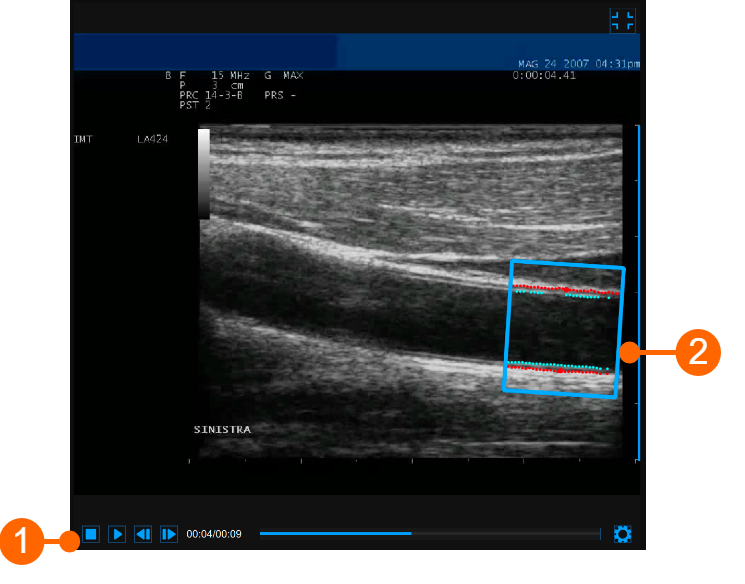

The video window shows the video signal from your ultrasound system. The points of the Lumen-Intima interface and the Media-Adventitia interface are displayed within the ROI (2) in cyan color.

The video control bar (1) is located at the bottom of the window.